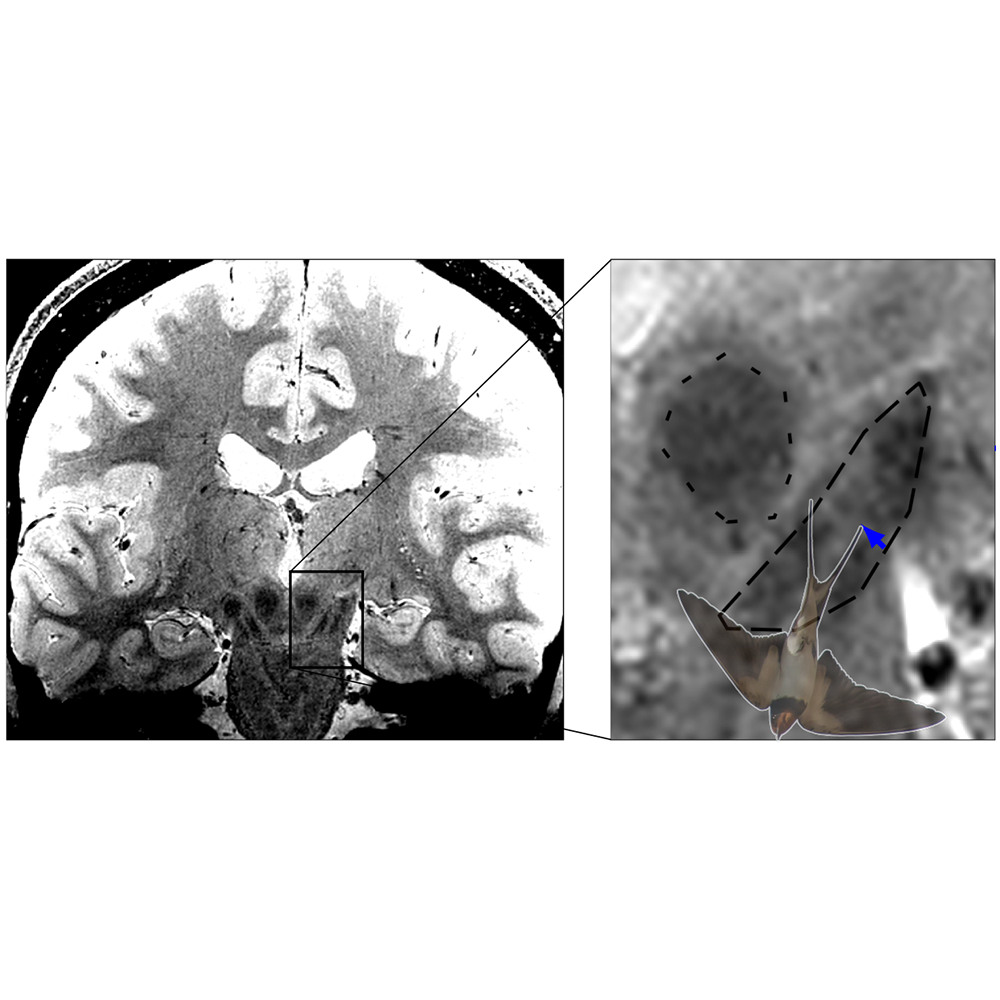

In Parkinson's disease, dopamine-producing nerve cells from the substantia nigra in the midbrain die. This causes movement disorders such as slowing, stiff muscles, and tremors in the patients. The nerve cells in nigrosome 1, which is within the substantia nigra, are affected particularly severely and early. With high-resolution MRI imaging it is possible to image the swallow-tail sign, which is located in the posterior third of the substantia nigra and, according to current textbook knowledge, corresponds to nigrosome 1. In healthy people, the MRI image shows a signal-rich elongated structure surrounded by signal-poor areas at the front and sides. This special shape is reminiscent of a swallow tail, which is where the name came from. According to the common interpretation of the sign, the death of neurons in nigrosome 1 in Parkinson's patients leads to the swallow-tail sign eventually no longer being recognisable. If this is the case, there is a high probability of Parkinson's disease.

Malte Brammerloh and his colleagues have now combined microscopic 3D examinations of human brains after death with MRI technology to show that nigrosome 1 and the radiological swallow-tail sign only partially overlap and are in fact very different. The scientists therefore argue that the swallow-tail sign should not be equated with the nigrosome 1 region. This allows a reinterpretation of the diagnostic swallow-tail sign and at the same time opens up new avenues for specific nigrosome imaging. Brammerloh adds, "We believe that with this new knowledge, it will be easier to understand how anatomy and MRI contrasts are related and how new MRI markers can be developed for the early diagnosis of Parkinson's."